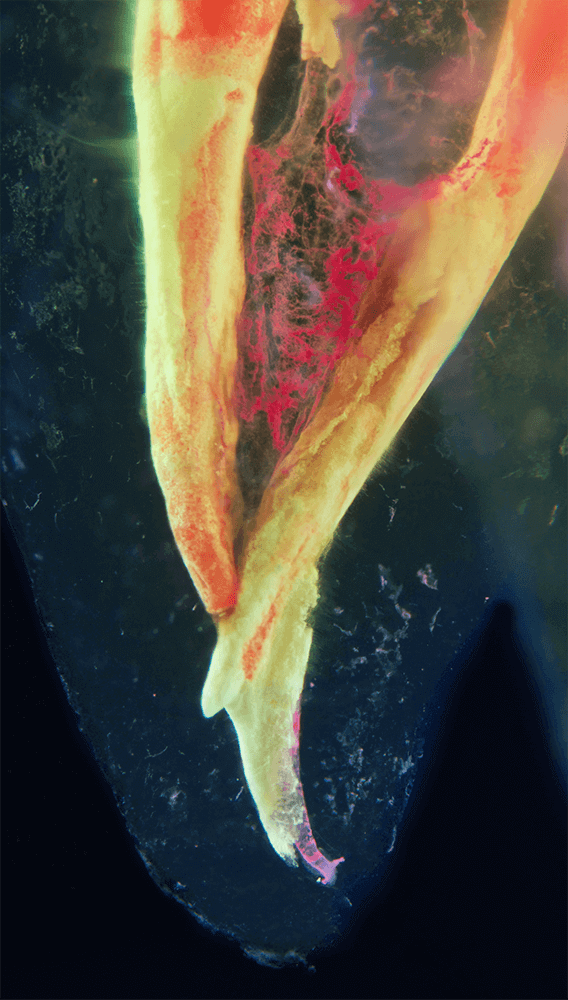

CLEARINGSERVICE bietet Ihnen die Möglichkeit, wurzelgefüllte Zähne mit der Technik des Transparentmachens untersuchen zu lassen. Das geht sehr einfach: Sie schicken uns den zu untersuchenden Zahn, dieser wird dann in ein transparentes Präparat überführt und mit hochwertiger Makrofotografie ausgewertet. Anschließend bekommen Sie die angefertigten Präparate zusammen mit der Fotodokumentation zugeschickt.

Die Bilder sind in verschiedenen Größen wählbar und auch als POPART-Variante erhältlich. Sie sind hervorragend geeignet für die Beratung von Patienten vor endodontischen Behandlungen, aber auch ein beliebter Eyecatcher im Wartezimmer. Außerdem haben die Bilder einen bedeutenden Stellenwert für die Erforschung der Pulpatopografie und für die Lehre im Bereich der Endodontie.